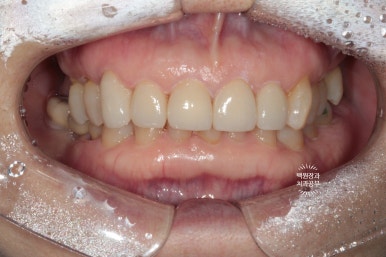

처음 내원하셨을 때 정면 사진입니다.

딱 봐도 위 대문니 두개에 큼지막한 세로 금이 관찰되네요. 환자분의 걱정 포인트이자, 콤플렉스였던 앞니 금.

생긴지 오래 되었을터인데, 시간이 흘러 착색까지 생겨버렸습니다. 50년 이상 사용한 치아에는 크랙이 많이 생길 수 있죠.

이렇게해서 두 번 수정한 앞니 지르코니아 크라운입니다.

처음에 비해 훨씬 가지런해지고 여성스러운 모양을 가진 치아로 완성되었네요!

치료 전과 후를 비교해보았을 때, 대문니에 있던 세로 금이 깔끔하게 해결되었고 밝아진 치아의 색상은 훨씬 더 환한 인상을 주게 되었습니다.